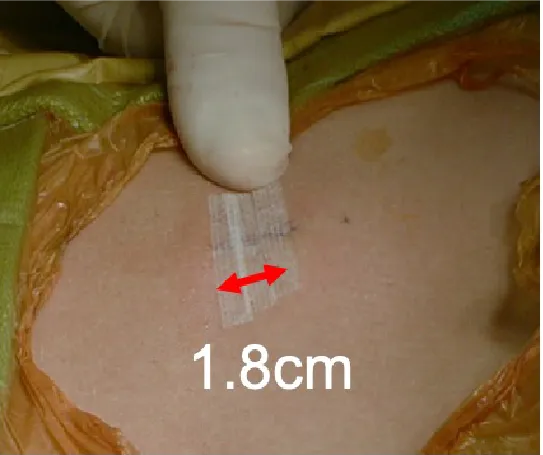

腰椎椎間板ヘルニアに対するMED法

-

モニターを見ながら行う手術風景 -

小さな傷で手術可能 -

MRI(左:術前 右:術後)